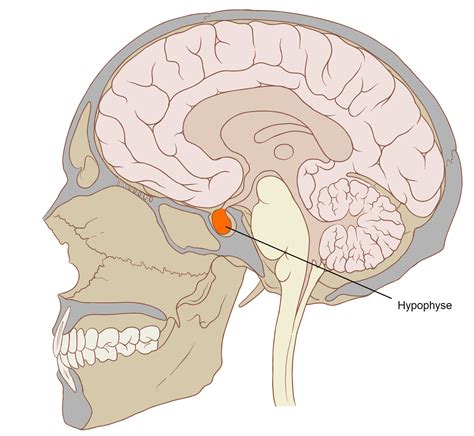

Sheehanov sindrom je redka, a resna poporodna endokrinopatija, ki nastane zaradi poškodbe hipofize, ki jo povzroči huda poporodna krvavitev ali šok med porodom. Hipofiza, pogosto imenovana "glavna žleza", igra ključno vlogo pri uravnavanju različnih hormonov, ki nadzorujejo rast, razmnoževanje, metabolizem in odzive na stres. Ko je pri Sheehanovem sindromu hipofiza poškodovana, se ti hormoni ne proizvajajo ustrezno, kar vodi do številnih hormonskih pomanjkljivosti, ki lahko vplivajo na zdravje ženske.

Vzroki za Pojav Sheehanovega Sindroma

Sheehanov sindrom se pojavi zaradi hude izgube krvi (poporodna krvavitev) ali šoka med porodom ali po njem, kar omejuje prekrvitev hipofize. To pomanjkanje krvnega pretoka lahko povzroči nepravilno delovanje žleze ali pa ta postane trajno poškodovana. Stanje je pogostejše v regijah, kjer so zdravstveni viri omejeni, poporodna krvavitev pa ni pravočasno zdravljena.

Ker ta žleza raste in se med nosečnostjo skoraj podvoji, je med porodom bolj občutljiva na poškodbe ali na včasih imenovan "šok". Če so celice hipofize poškodovane ali odmrejo (nekroza), se lahko število hormonov, ki jih proizvaja, zmanjša, kar povzroči hipopituitarizem. V tem primeru lahko opazimo stanja, kot je pomanjkanje posameznih hormonov hipofize ali popolni hipopituitarizem. Podobno ščitnica in nadledvična žleza celo izgubita sposobnost sproščanja zadostne količine hormonov, upadejo pa tudi funkcije teh prizadetih organov. Zato Sheehanov sindrom med nosečnostjo velja za enega najpogostejših vzrokov hipopituitarizma pri nosečnicah.